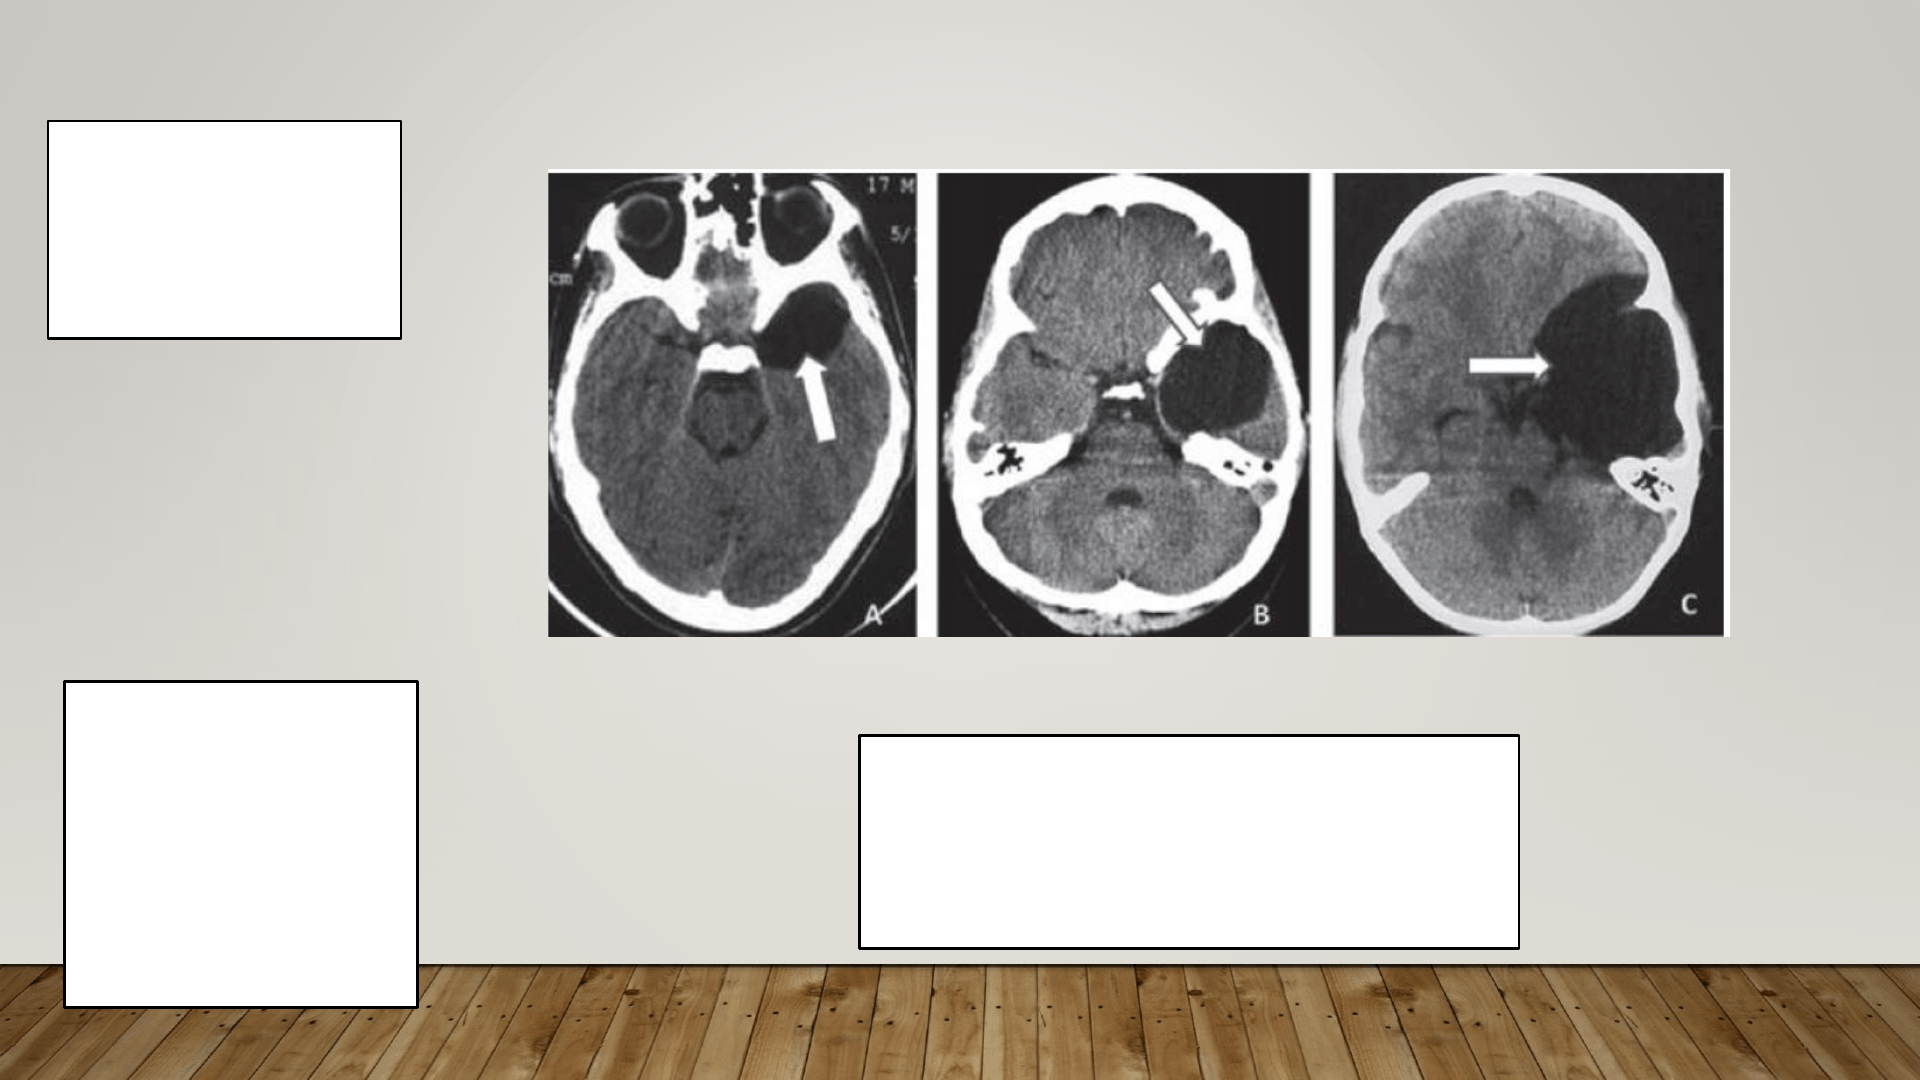

El término, quiste porencefálico se utiliza para definir una

cavidad en el parénquima cerebral y que pueden comunicar o

no con los ventrículos, llenos de LCR, en el parénquima.

Las cavidades a menudo se comunican con un ventrículo, pero también

pueden ser quistes cerrados (es decir, no comunicantes) llenos de líquido.

Puede haber un aumento de la presión intracraneal e hidrocefalia

progresiva en la porencefalia, especialmente en las formas no comunicantes,

aunque es raro.